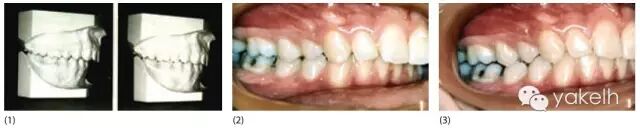

¤¤一些学者认为颅颌功能紊乱与错密切相关,而另一些学者坚称错牙合对TMD的风险没有影响。形态牙合与功能牙合的区别是对这种分歧的一个解释。图15.1的患者是安氏Ⅰ类牙合关系,主诉是肌肉疼痛和紧张性头痛。当该患者戴用平面咬合板时,她的牙合关系从中性牙合变为远中牙合。显然她存在双重牙合,同时肌电检查显示接位的肌电活动强度要显著高于该患者被要求咬紧牙时的肌电强度。在这两个颌位拍摄的X线片证实当该患者咬合于安氏Ⅰ类牙尖交错位时,她的髁突发生了前下移位,而当她试图建立后退接触位时,髁突回到关节窝正中。我们通常在最大牙尖交错位对患者进行观测和记录,但该颌位不一定代表一个与功能牙合相协调的颌位,这可能是评价牙合与TMD相关性时的一个混杂因素。

图15.1 (1)两个不同颌位的研究模型。左侧的模型显示的是患者被要求将牙齿咬合在一起时,自发咬合形成的牙合,右侧模型显示的是患者戴用平面咬合板一段时间后建立的后退接触位的咬合。(2,3)相同情况下的临床表现。